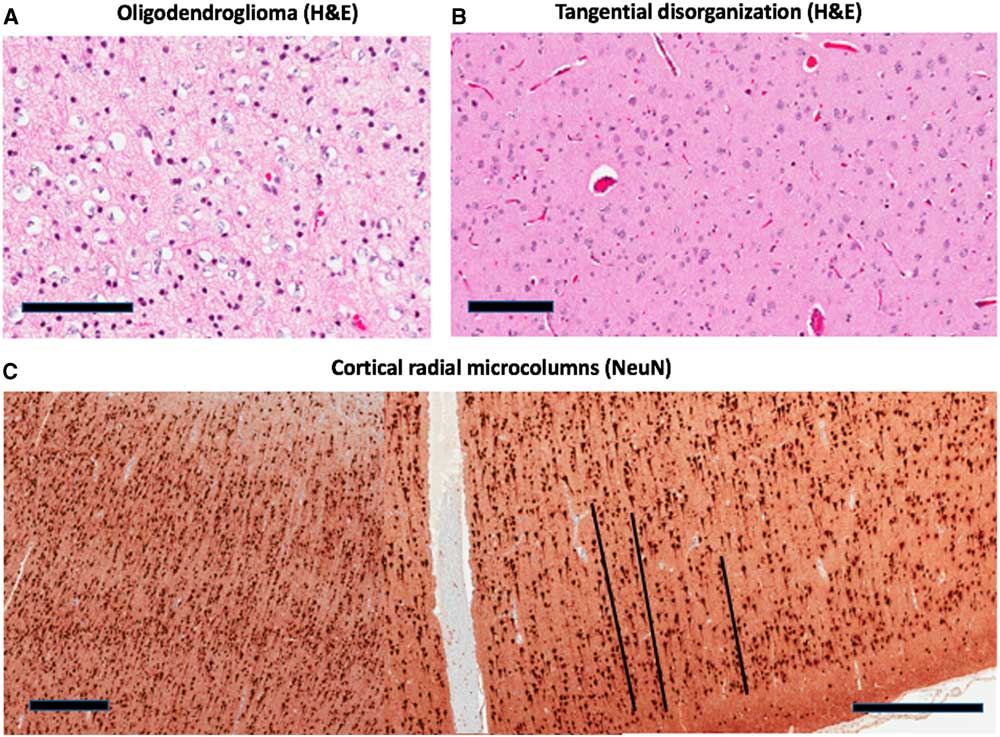

The right frontal lobe neoplasm consisted of cells with round to oval nuclei with minimal atypia. Many cells displayed perinuclear halos (Figure 2A). Some of these infiltrated the adjacent cortex, forming perineuronal aggregates. One mitosis was noted in the entire specimen. These appearances are those of a low-grade oligodendroglioma. A higher-grade was excluded by the absence of more than a few mitoses, necrosis, and vascular proliferation. Other low-grade gliomas were excluded by the absence of dysplastic ganglion cells or perivascular inflammation, specific glioneuronal elements, lack of Rosenthal fibres and eosinophilic granular bodies. Immunohistochemical staining showed that the neoplastic cells were positive for the R132H mutant form of isocitrate dehydrogenase (IDH)-1. Ki67 (a proliferation marker) stained no more than 5% of the nuclei in the most heavily stained region. Glial fibrillary acidic protein was mostly negative around the cells, with a rare perinuclear rim. Fluorescent in-situ hybridization studies showed co-deletions of chromosomes 1p and 19q, a molecular hallmark of oligodendroglioma. Cells also exhibited retained nuclear staining for Alpha-Thalassemia/Mental Retardation X-linked (ATRX). This confirmed the diagnosis of oligodendroglioma, IDH-mutant and 1p/19q-codeleted (World Health Organization Grade II).Reference Louis, Perry and Reifenberger 6 The adjacent right frontal cortex showed both tangential and radial disorganization of neurons, the defining features of FCD (Figure 2B, C). Histologically, radial microcolumns are defined as eight or more neurons aligned in a vertical direction, where the section is stained with the neuronal marker NeuN (Neuronal Nuclei), oriented perpendicular to the pial surface.Reference Blümcke, Thom and Aronica 3 Aligned neurons present with a small diameter and cell size of <250 μm2. As emphasized by the black lines in Figure 2C, there are at least three cortical microcolumns present, with at least eight neurons in each. The tangential disorganization is based on the presence of large and small neurons in close proximity, clusters of neurons, and neurons orientated in varying directions, instead of the normal orientation of the axon hillock towards the cortical surface (Figure 2B). The neurons were not themselves dysmorphic (with clumped Nissl substance or nuclear abnormalities including binucleate neurons) and balloon cells were not identified. The cortex was adjacent to the neoplasm, and not infiltrated by it, as indicated by negative staining for mutant IDH-1. By current classification, this is defined as FCD Type IIIb.Reference Blümcke, Thom and Aronica 3

Figure 2 Pathologic features of the case. (A) shows the oligodendroglioma with perinuclear halos (H&E image). (B, H&E; C, NeuN) show focal cortical dysplasia in adjacent right frontal cortex. This consists of tangential (B) and radial (C) disorganization of neurons. Black lines are included in (C) next to each of three microcolumns. Scale bar=100 µm (A,B) or 500 µm (C). H&E=haematoxylin and eosin; NeuN=Neuronal Nuclei.